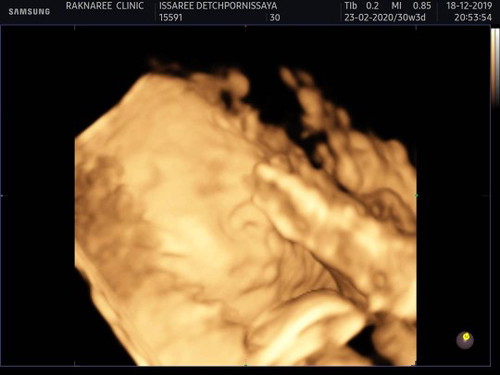

เมื่อวานไปอัลตร้าซาวด์ 4 มิติ ที่รักษ์นรีคลีนิคมาค่ะ คุณหมอและเจ้าหน้าที่ทุกคนพูดจาดีมาก เป็นกันเองสุดๆ ซาวด์รอบแรก ไม่เห็นหน้าเพราะนอนคว่ำหน้า คุณหมอเลยให้ไปเดินเล่นประมาณ 15 นาที แล้วมาซาวด์ใหม่ รอบสอง ก็ยังคว่ำอยู่ คุณหมอเลยบอกให้พาลูกไปกินไอติม เพราะลูกอาจจะอยากได้น้ำตาลมากระตุ้น เผื่อจะตื่น ? รอบสาม เริ่มหันข้างนิดๆ เลยได้มาแค่ภาพที่เห็น คุณหมอและพยาบาลก็ช่วยกันกระตุ้น ช่วยกันกวน ก็หันหน้านะคะ แต่หันหนี ยิ่งกระตุ้นยิ่งหลบ หลบจนหน้าติดกับผนังมดลูกชนิดที่ว่าไม่มีช่องว่างเลย ครบ 3 รอบแล้ว ใช้เวลาประมาณ 1 ชั่วโมงครึ่ง ตั้งแต่ทุ่มครึ่งถึงสามทุ่ม ได้มาครึ่งหน้าก็ยังดี ดีกว่าไม่เห็นอะไรเลย 55555 เสียเงินซาวด์แล้ว คุณหมอจะพยายามให้เราได้ภาพสวยๆ กลับไปค่ะ ?? เผื่อใครสนใจอัลตร้าซาวด์ 4 มิติ ขอแนะนำที่นี่เลยนะคะ เห็นแนะนำกันหลายคนแล้ว พอมีเวลาก็เลยลองไปดู ดีจริงๆ ค่ะ ?